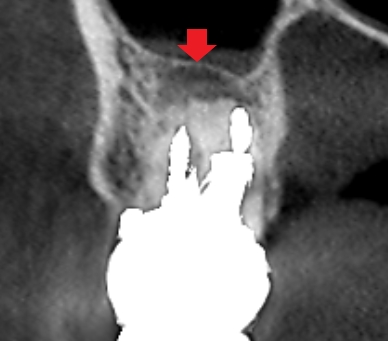

上顎第二大臼歯の冠状断のCT画像です。

赤い矢印の先に膿の影がみられます。

6カ月後の経過観察時の冠状断のCT画像です。矢印の先にあった膿の影が消え、歯槽骨が再生しています。